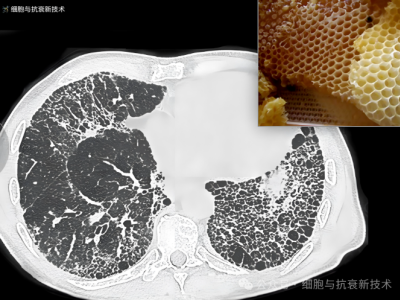

外泌體霧化可治療肺部結(jié)節(jié)及肺纖維化

2019年新冠疫情后,大家對(duì)肺部損傷比較關(guān)注,加之生活工作壓力以及檢測(cè)技術(shù)的進(jìn)步,使結(jié)節(jié)成為體檢報(bào)告上出現(xiàn)的高頻詞匯,其中包括肺部結(jié)節(jié),結(jié)節(jié)的出現(xiàn)給部分人群增添了焦慮。外泌體作為先進(jìn)治療藥品,是當(dāng)前生